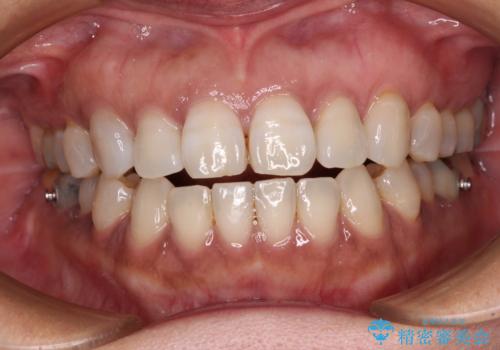

- 上下前歯の隙間を気にして来院された患者様です。

開咬の治療は、前歯を閉じるように動かすとともに、上下臼歯を圧下(骨内にめり込ませる)させることで進めて行きます。

インビザラインは臼歯の圧下を効果的に行えるため、インビザラインを用いて矯正治療を行うこととしました。

また、下顎大臼歯に根管治療が必要な歯があるため、矯正治療と並行して治療を行い、矯正後に補綴治療することとしました。